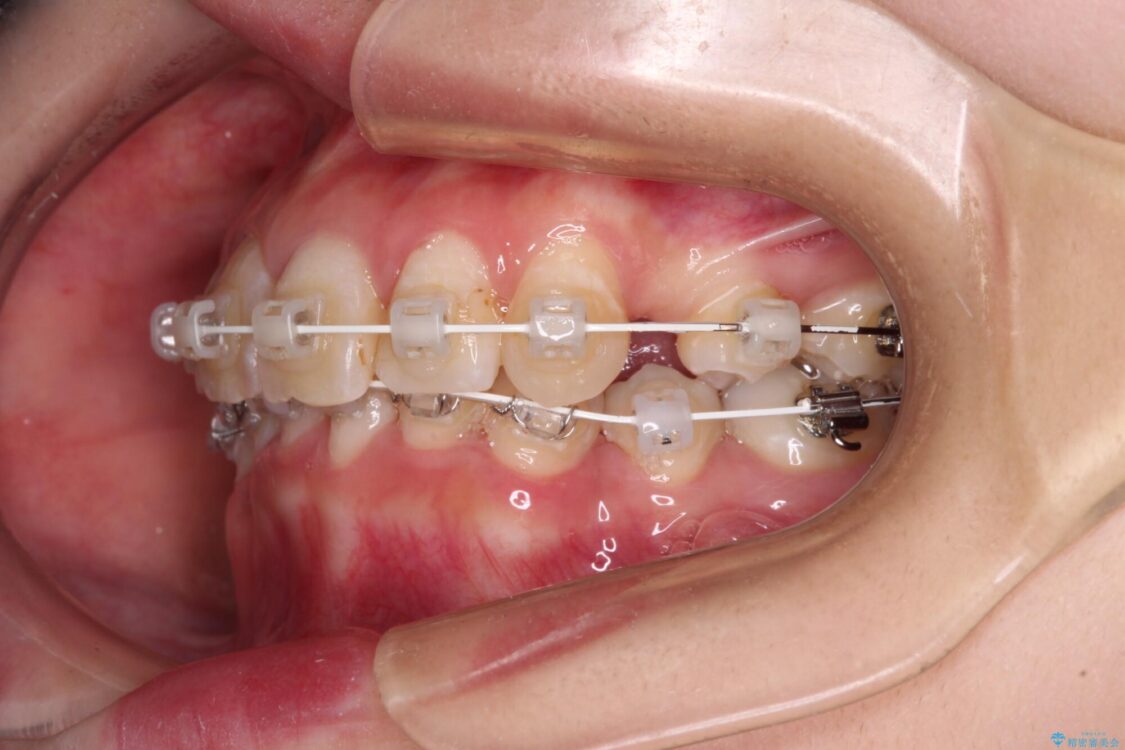

治療途中

• デコボコと深い咬み合わせ ワイヤー装置での抜歯矯正 治療途中画像

下顎の叢生を解消するために抜歯が必要であり、奥歯の咬み合わせや口元の印象から、上顎も同様に抜歯と判断し、上下左右の第1小臼歯4本抜歯してワイヤー装置にて矯正治療を行うこととしました。

咬み合わせが深く、そのままでは上顎の抜歯スペースが閉じきらない可能性があったため、治療初期から深い咬み合わせを改善させるように試みました。